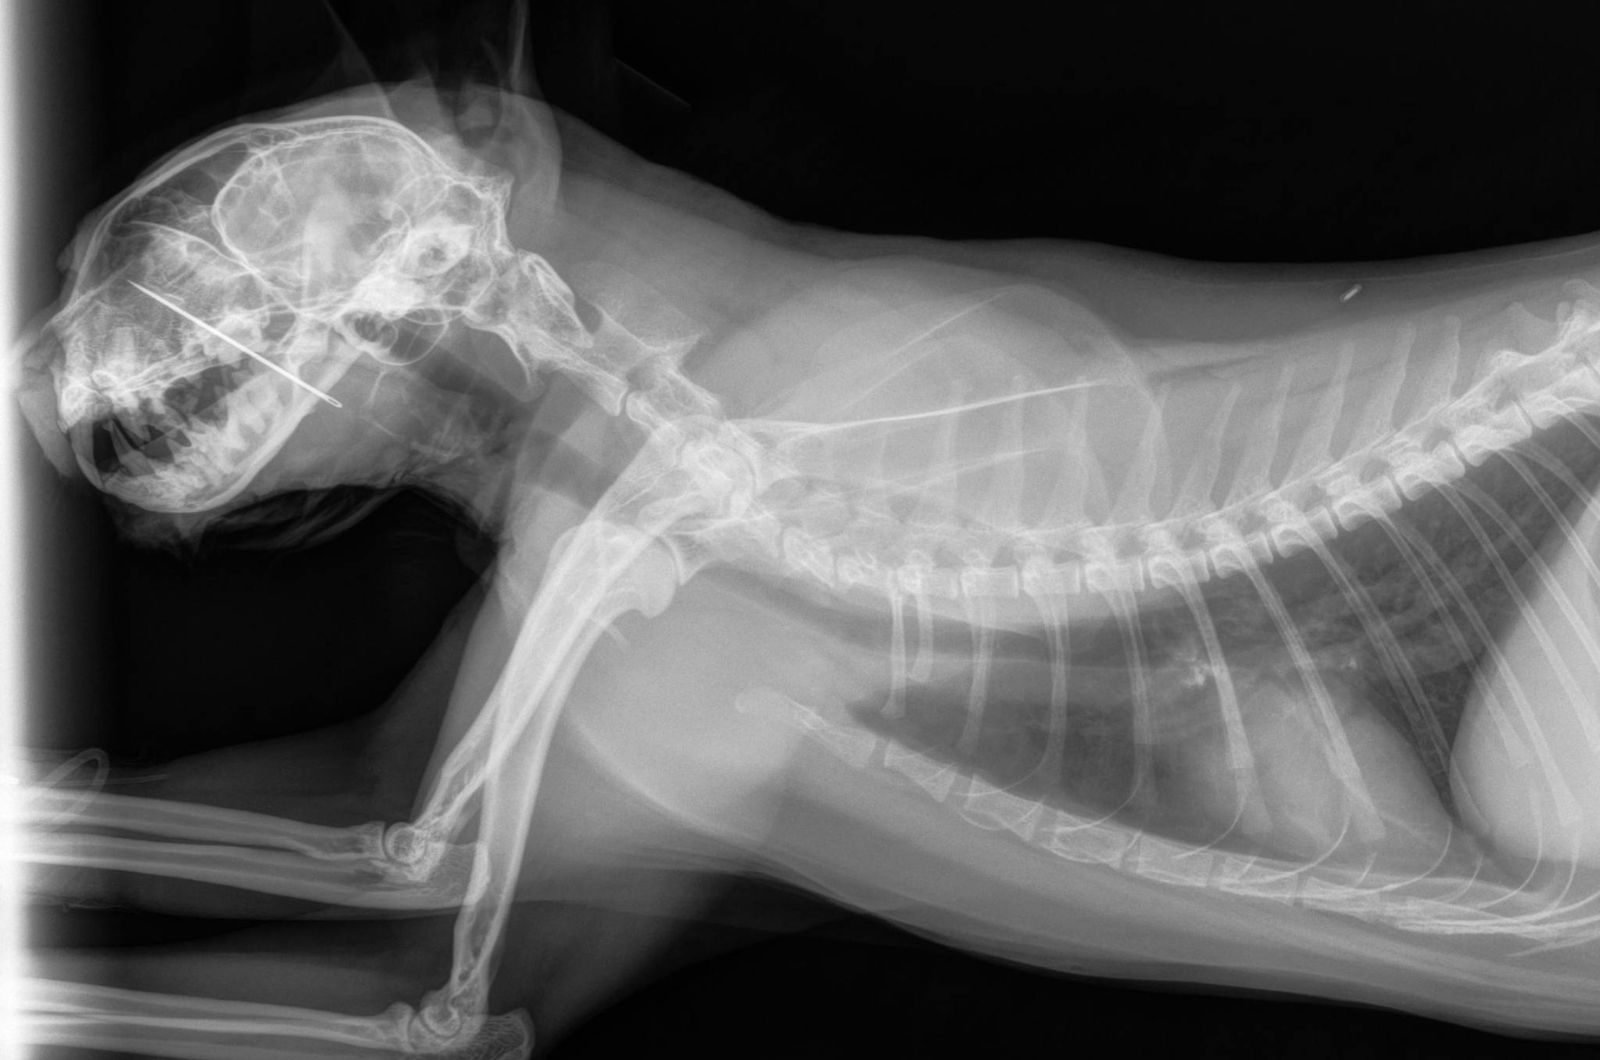

That’s when the shocking discovery was made. An X-ray revealed the sewing needle stuck firmly in his hard palate, extending into his nasal cavity.

It was a sight that made even the experienced staff pause. But the team wasted no time. With precision and skill, they carefully removed the needle before it could cause more damage.